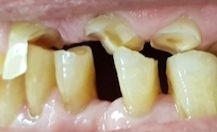

Bruxismus, Zigaretten und die schwierige Mundhygiene sind schuld an den Misserfolgen.

67-jähriger Patient (29.01.2026 / 2688)

Der Patient hat einen ausserordentlich starken Händedruck, und es sind ihm schon zwei andere Höcker abgebrochen. Die palatinalen Höcker der oberen ersten Prämolaren werden wegen Hyperbalancen zur Seite gedrückt und brechen häufiger ab als die anderen.

links: Der Prämolar mit dem abgebrochenen Höcker.

rechts: Der 0.6 mm kleine Rosenbohrer verbessert die Haftung des Komposits. Dazu bohrt man mit ihm dem Rand des Defektes entlang eine Serie von kleinen Löchern. Diese bewahren die Füllung vor dem Abrutschen wie die Nägel einer Schuhsohle.